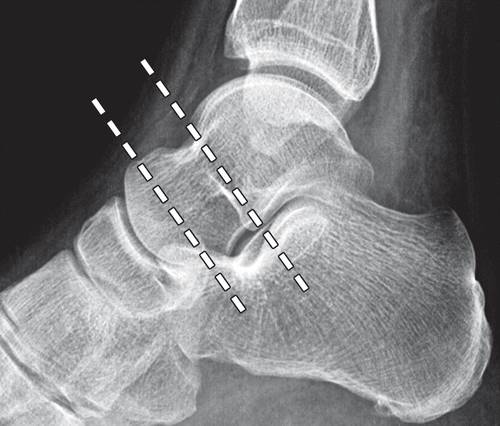

传统上认为最常见的距骨骨折(13,14),颈部骨折最近显示仅占全部骨折骨折的5%(9)。 这种差异可能是由于在颈部和身体骨折之间缺乏明确的区别。 广泛接受的定义是基于下骨折线的位置。 如果骨折线前或劣于距骨和距骨圆顶软骨的横向过程中,它被划分为距骨颈骨折(图4)(15)。

图4b距骨颈部的边界。 距骨的三维重建的CT图像(a)和外侧踝部的X射线照片(b)示出了距骨头,颈部和身体之间的分割(虚线)。 距骨体部骨折是由位于侧向进程中或后一个下骨折线定义。